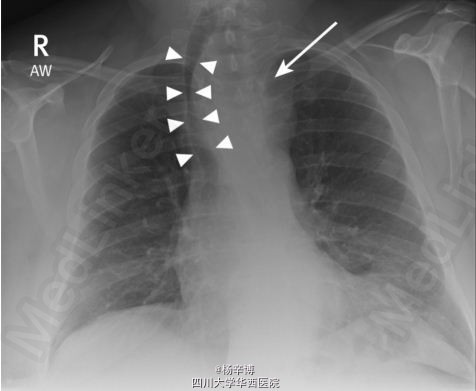

患者体格检查未见异常,常规血液检查、心电图未见异常。 胸片、胸部CT异常 器官明显右偏,上纵隔见均质密度影(箭头) 前纵隔巨大包块,甲状腺来源可能